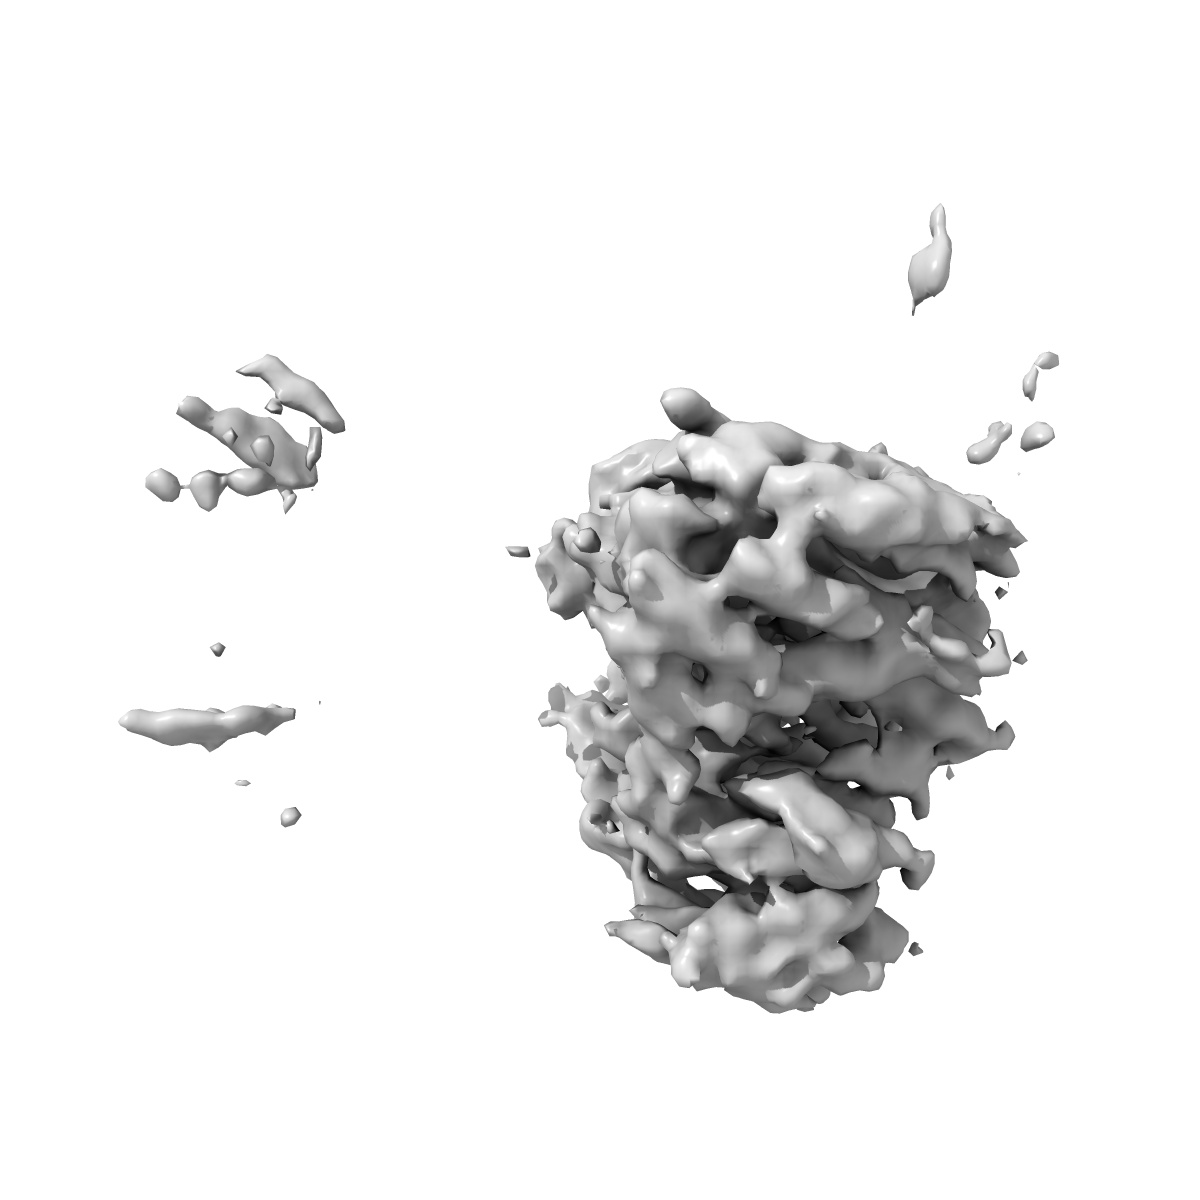

Rapid screening cryo-EM map of CAK bound to BS-181 (grid VC8-1, 1hr collection)

Single-particle3.7 Å

Sample: CDK-activating kinase

High-resolution cryo-EM of the human CDK-activating kinase for structure-based drug design.

(2024) Nat Commun , 15 , 2265 - 2265